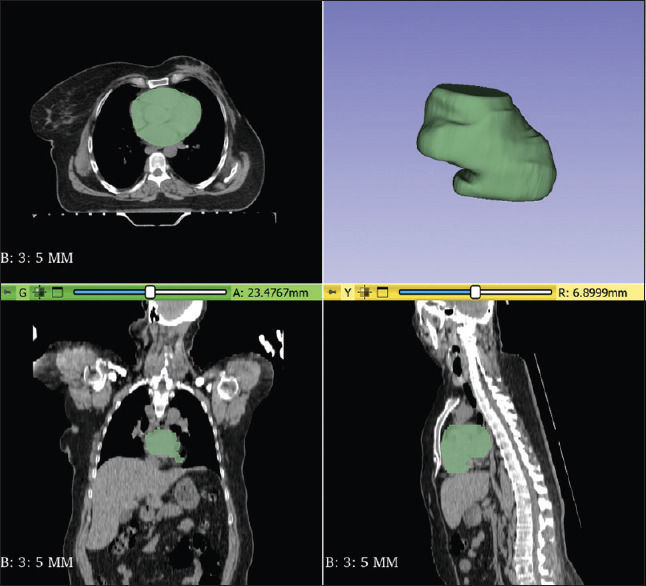

Materials and methods: We selected 54 breast cancer patients who received left-sided chemoradiation therapy and had a low risk of natural heart failure according to the Framingham score. We compared echocardiographic patterns and ejection fraction (EF) measurements before and 3 years after radiotherapy for each patient. Based on these comparisons, we evaluated the incidence of heart failure 3 years postchemoradiation therapy. For machine learning (ML) modeling, we first segmented the heart as the region of interest in CT images using a deep learning technique. We then extracted radiomic features from this region. We employed three widely used classifiers - decision tree, K-nearest neighbor, and random forest (RF) - using a combination of radiomic, dosimetric, and clinical features to predict chemoradiation-induced heart failure. The evaluation criteria included accuracy, sensitivity, specificity, and the area under the receiver operating characteristic curve (area under the curve [AUC]).

Results: In this study, 46% of the patients experienced heart failure, as indicated by EF. A total of 873 radiomic features were extracted from the segmented area. Out of 890 combined radiomic, dosimetric, and clinical features, 15 were selected. The RF model demonstrated the best performance, with an accuracy of 0.85 and an AUC of 0.98. Patient age and V5 irradiated heart volume were identified as key predictors of chemoradiation-induced heart failure.